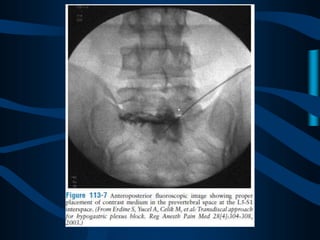

ABORDAJE

TRANSDISCAL

CON UNA AGUJA